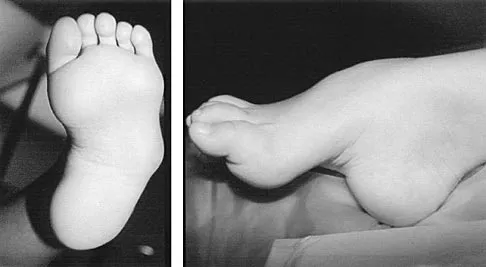

A 6-year-old girl has the bilateral foot deformity shown in Figure 1. There is no family history of disease. Examination reveals fixed hindfoot equinus, and muscle function testing shows strong posterior tibial function, fair plus anterior tibial function, poor peroneal function, and strong gastrocnemius function. A Coleman block test shows a correctable hindfoot. Nerve conduction velocity studies show diminished function in the peroneal and ulnar nerves on both sides. Pathologic changes found in a sural nerve biopsy include "onion bulb" formation, and DNA testing confirms the presence of a mutation in the MPZ gene, consistent with hereditary motor sensory neuropathy type III (HMSN-III). What is the best course of action?